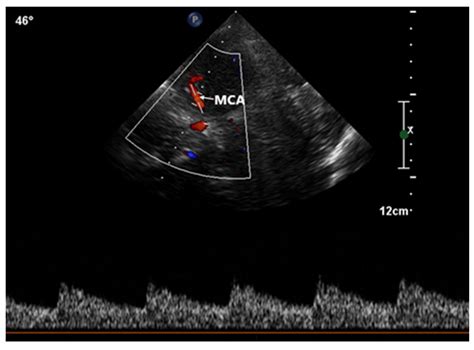

Diagnostic imaging and testing are crucial for confirming the presence and severity of the shunt. Clinicians typically utilize the following tools:

Echocardiography Visualizes blood flow and identifies structural septal defects.